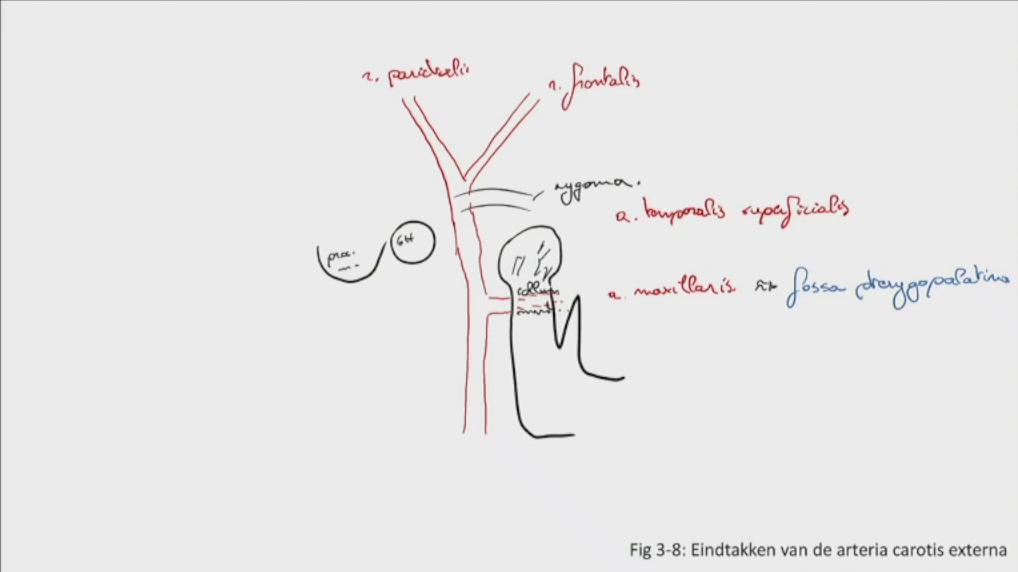

Fig 3.08: a. carotis externa - eindtakken

proc. mastoideus meatus acusticus externus arcus zygomaticum = zygoma collum mandibulae glandula parotis a maxillaris (langs m. pterygoideus naar fossa pterygopalatina) -

a temporalis superficialis

onder glandula parotis r frontalis r parietalis